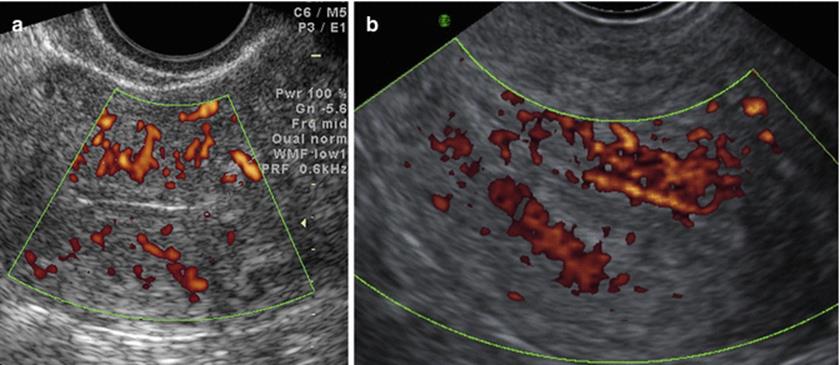

Endometrial and Subendometrial Vascularity

Endometrial and subendometrial vascularity indices (Fig. 2.20) are high throughout the follicular phase; peak value is reached for 3 days before ovulation and reduces to a nadir 5 days after ovulation and then increases again during the luteal phase [38]. Relative endometrial hypoxia during the implantation phase aids blastocyst implantation. Patients who get pregnant have a lower RI (0.53 vs. 0.64) and it was observed that the hyperechoic endometrium had a higher incidence of absent subendometrial blood flow [39] and in these cases, no pregnancy was reported [40].

Fig. 2.20

(a, b) Subendometrial blood flow

Endometrial Vascularity Zones by Applebaum (Fig. 2.21)

Fig. 2.21

Endometrial vascularity zones

· Zone I – Myometrium surrounding the endometrium

· Zone II – Hyperechoic endometrial edge

· Zone III – Internal endometrial hypoechoic zone

· Zone IV – Endometrial cavity

Conception rates are very low when vascularity is not seen in Zone III–IV.